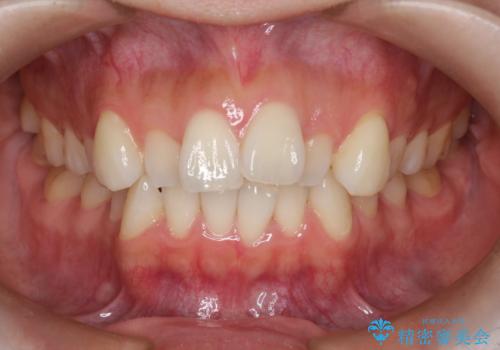

【審美装置】前歯のがたがたを治したい

- 前歯の凸凹と口元の突出感を主訴に来院されました。

臼歯関係が上顎前突傾向のため、上の小臼歯を抜歯してワイヤー矯正を行なっております。

下顎の叢生はIPRを行なって配列しています。